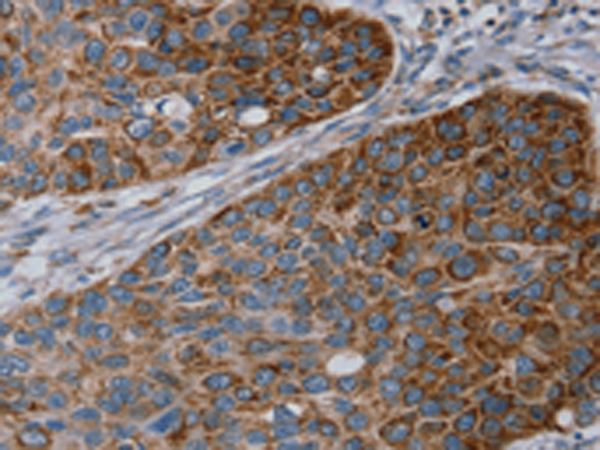

分类: 科研抗体货号: P08686别名: GISP; RELP; REG-IV应用: IHC反应种属: Human